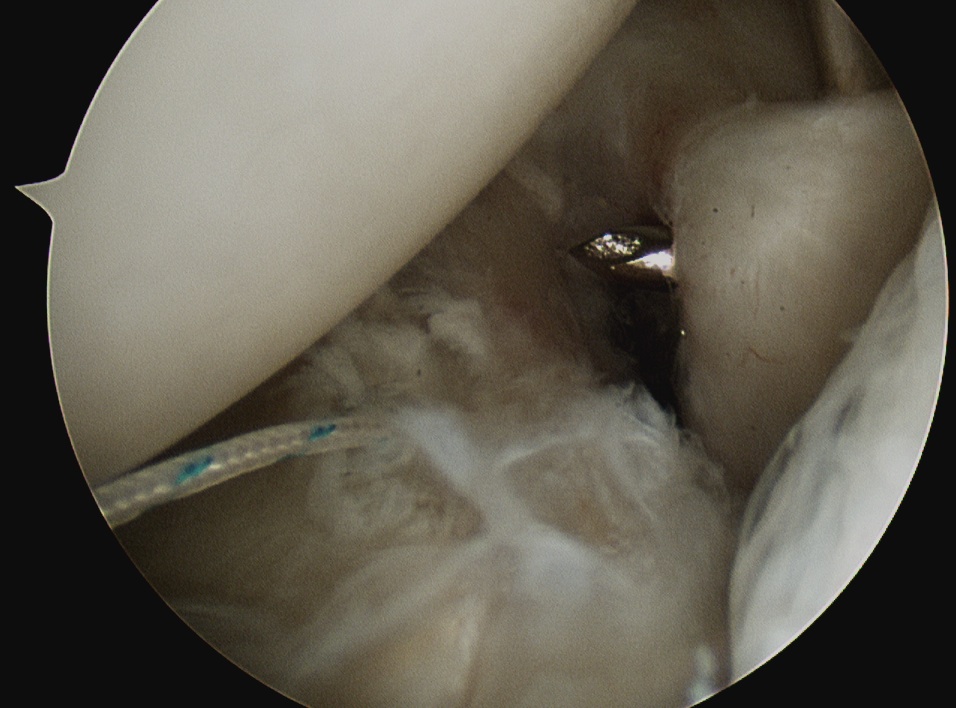

Insert anchors

Inferior anchor at 5.30 o'clock

- curved anchor guide / trans-subscapularis

- on rim of glenoid

Other anchors typically at 3 and 4 o'clock

Arthroscopy Bankart Anchor Drill GuideInferior Glenoid Anchor